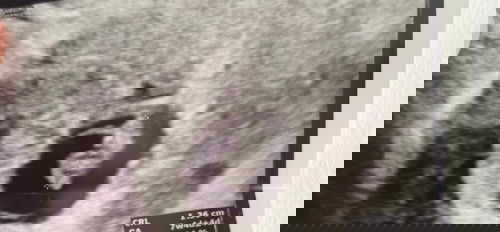

Hi mamas. I had light spotting this morning when i woke up and gradually it got more. Till this moment fills half a normal pad with slight clots. Went to private gynae and he can’t seem to find heartbeat via tummy scan and the scan shows smaller than supposed size. I’m supposed to be 9weeks but scan shows only 7 weeks 5 days. I went to see the same gynae 2 weeks ago, and he did vaginal scan was able to hear heartbeat. He suspects that baby have stop growing and i should just monitor and see if it naturally “come out” I’m still in denial stage.. should i consider second option and head to NUH a&e? Anyone gone through the same experience before? 🥺 #advicepls #firstbaby